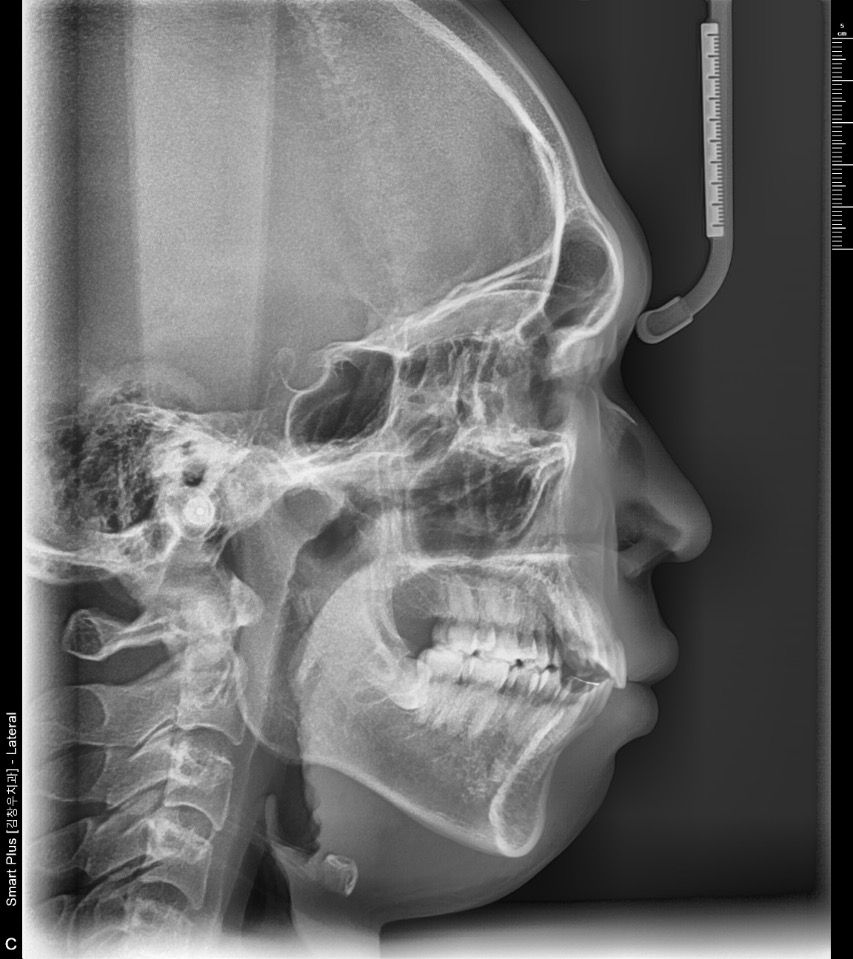

무턱인지 하악왜소증인지 궁금합니다

무턱인지 하악왜소증인지 궁금합니다 돌출입 때문에 치아교정했는데 1년째 입이 들어가는것같지가 않아 낮은코와 턱때문인거같다는 생각이 들더라고요

하악이 후퇴되거나 왜소증 가능성이 있습니다.

하악골의 전방 돌출이 부족하여 길이도 짧아보이는 것 같습니다.

따라서 무턱 인상도 유발하게 되는 것 같습니다.

또한 비순각(코끝-윗입술사이의 각도)도 각도가 아쉽습니다.

코끝높이를 올려주는것이 도움이 될 것 같습니다.